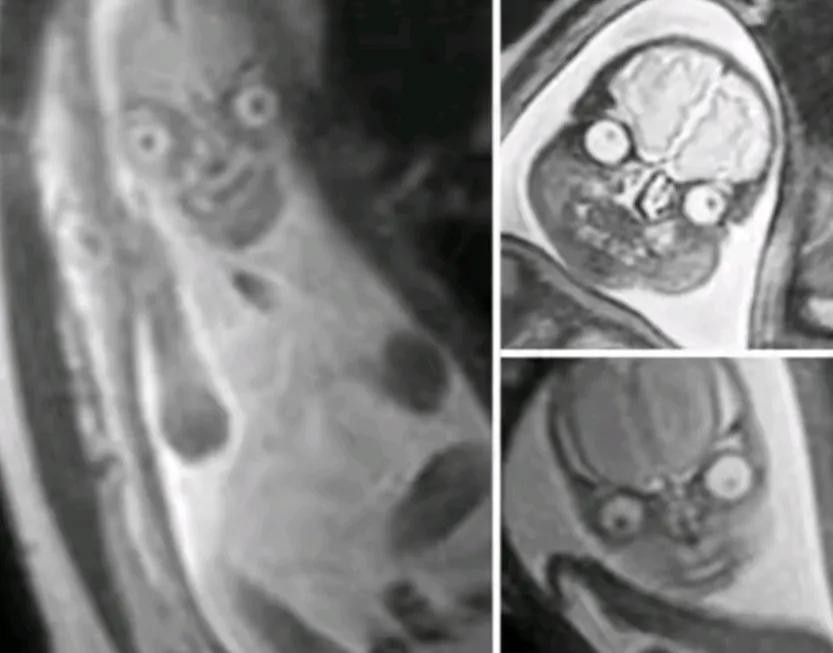

九,磁共振扫描出来的婴儿面部,是不是看着有点吓人。